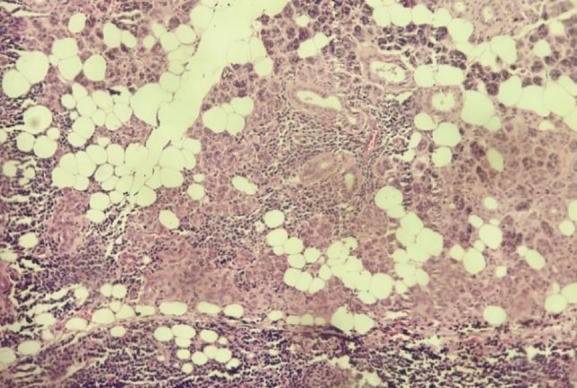

鉴于腮腺占位性病变持续存在,为明确诊断并进行治疗,患者在全身麻醉下接受了“右侧腮腺浅叶切除术”,并对右侧腮腺标本进行病理活检,提示MCL。镜下显示,正常的腮腺腺体组织被大小不一、形态单一的非典型淋巴细胞浸润——细胞核质比高,细胞核不规则、深染,染色质呈团块状,核仁不明显,胞质稀少。肿瘤细胞广泛浸润至周围脂肪及骨骼肌(图2,3)。

11111.jpg

图3. 400倍镜下(HE染色)可见形态单一的非典型淋巴细胞,核质比高,核深染,浸润周围组织